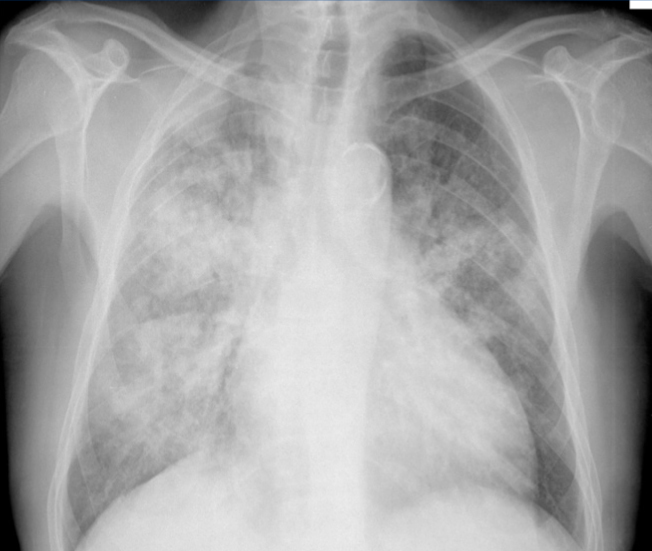

A 17-year-old boy presents to the emergency department of a hospital located in the town of Recuay (which is situated at 3,400 meters above mean sea level [MAMSL]) in the Ancash Region (Peru), 48 hours after returning from a 21-day stay in Lima (the capital city of Peru at 0 MAMSL). The patient has no previous medical history. His current complaints include cough, dyspnea at rest, hemoptysis, chest pain, and vomiting. His vital signs include: blood pressure 90/60 mm Hg; heart rate 149/min; respiratory rate 37/min; temperature 36.5°C (97.7°F); and O2 saturation 71%. Physical examination reveals polypnea, perioral cyanosis, intercostal retractions, and diffuse pulmonary crackles. His laboratory results are as follows: Hemoglobin 19.2 g/dL Hematocrit 60% Leukocytes 13,000 (Bands: 12%, Seg: 78%, Eos: 0%, Bas: 0%, Mon: 6%) Urea 25 mg/dL Creatinine 0.96 mg/dL A chest X-ray is shown. Which of the following statements is true and most likely regarding this patient’s condition?